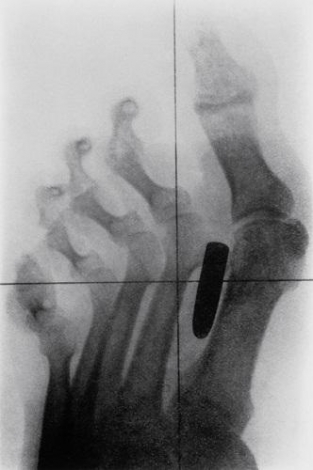

8912143325477243458.jpg

這張X照片展示了一顆釘子穿過了一位男子的食指和中指。